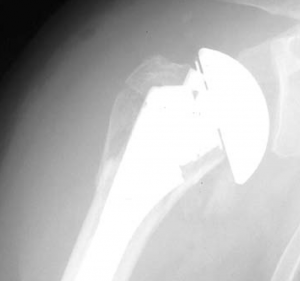

In diesem Fall kann das Gelenk durch ein sog. inverses Prothesen-System nach Prof. Paul Grammont ersetzt werden. Hierbei wird eine „Halbkugel“ (Glenosphäre) auf die ursprüngliche Pfanne aufgeschraubt und eine konvex geformte „Humeruspfanne“ im Oberarmknochen fixiert (Abb. 48). Der Oberarm wird dadurch wieder nach „unten“ verlagert und die Funktion des M. deltoideus wird verbessert (Abb. 49).

Ist durch die Schwere der Verletzung jedoch mit Hilfe dieser Implantate keine gelenkerhaltende Operation möglich, besteht die Möglichkeit des Oberarmkopfersatzes durch eine Prothese (künstlicher Teilgelenkersatz) (Abb. 56, 57). In den letzten Jahren wurden für diese Art des Gelenkersatzes spezielle Prothesenmodelle entwickelt, die sich individuell auf die Fraktur abstimmen lassen. So ist der Prothesenkopf höhenverstellbar, um frakturbedingte Höhenverluste auszugleichen. Des Weiteren besitzt die Frakturprothese besondere Vorrichtungen, um die abgerissenen Rollhügel (Tuberculum majus und minus) an der Prothese in anatomischer Position zu refixieren. Dies ist wichtig, da an den Rollhügeln die Sehnen der Rotatorenmanschette ansetzen und damit erst eine Funktion der Schulter wieder hergestellt werden kann.

Eine Sonderstellung nimmt die Oberarmkalottentrümmerfraktur ein. Werden bei dieser Fraktur mehr als 40% der Gelenkfläche zerstört, ist auch hier der Gelenkflächenersatz mittels Oberarmkopfprothese (Abb. 57) angezeigt.